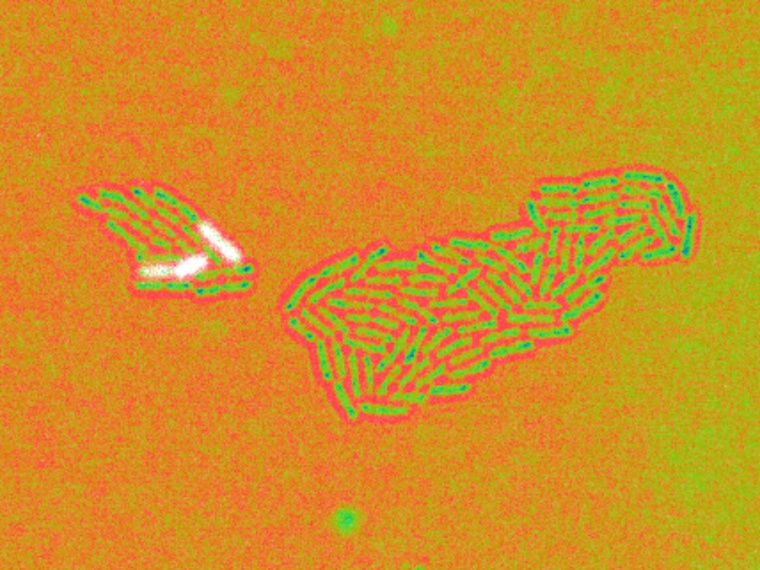

Mithilfe der Gentechnik konnten die Forschenden ein ON/OFF-Verhalten dieses Gens in einzelnen Bakterien der Population nachweisen: Einige wenige Zellen exprimieren dieses Gen in sehr hoher Konzentration, während die meisten dies nicht tun. Die Forschenden fanden heraus, dass diese Unterschiede durch epigenetische Schaltmechanismen entstehen – und eine Form der Erinnerung erzeugen, die über mehrere Generationen hinweg vererbt wird.

Die Wissenschaftler*innen kombinierten modernste Einzelzellanalysen, Live-Mikroskopie und mathematische Modellierung. Ihre Ergebnisse zeigen: Diese innerbakterielle Vielfalt kann sich schon aus kleinsten Zahlen an Bakterien entwickeln – etwa dann, wenn wenige Erreger durch eine Wunde gelangen oder eingeatmet werden.